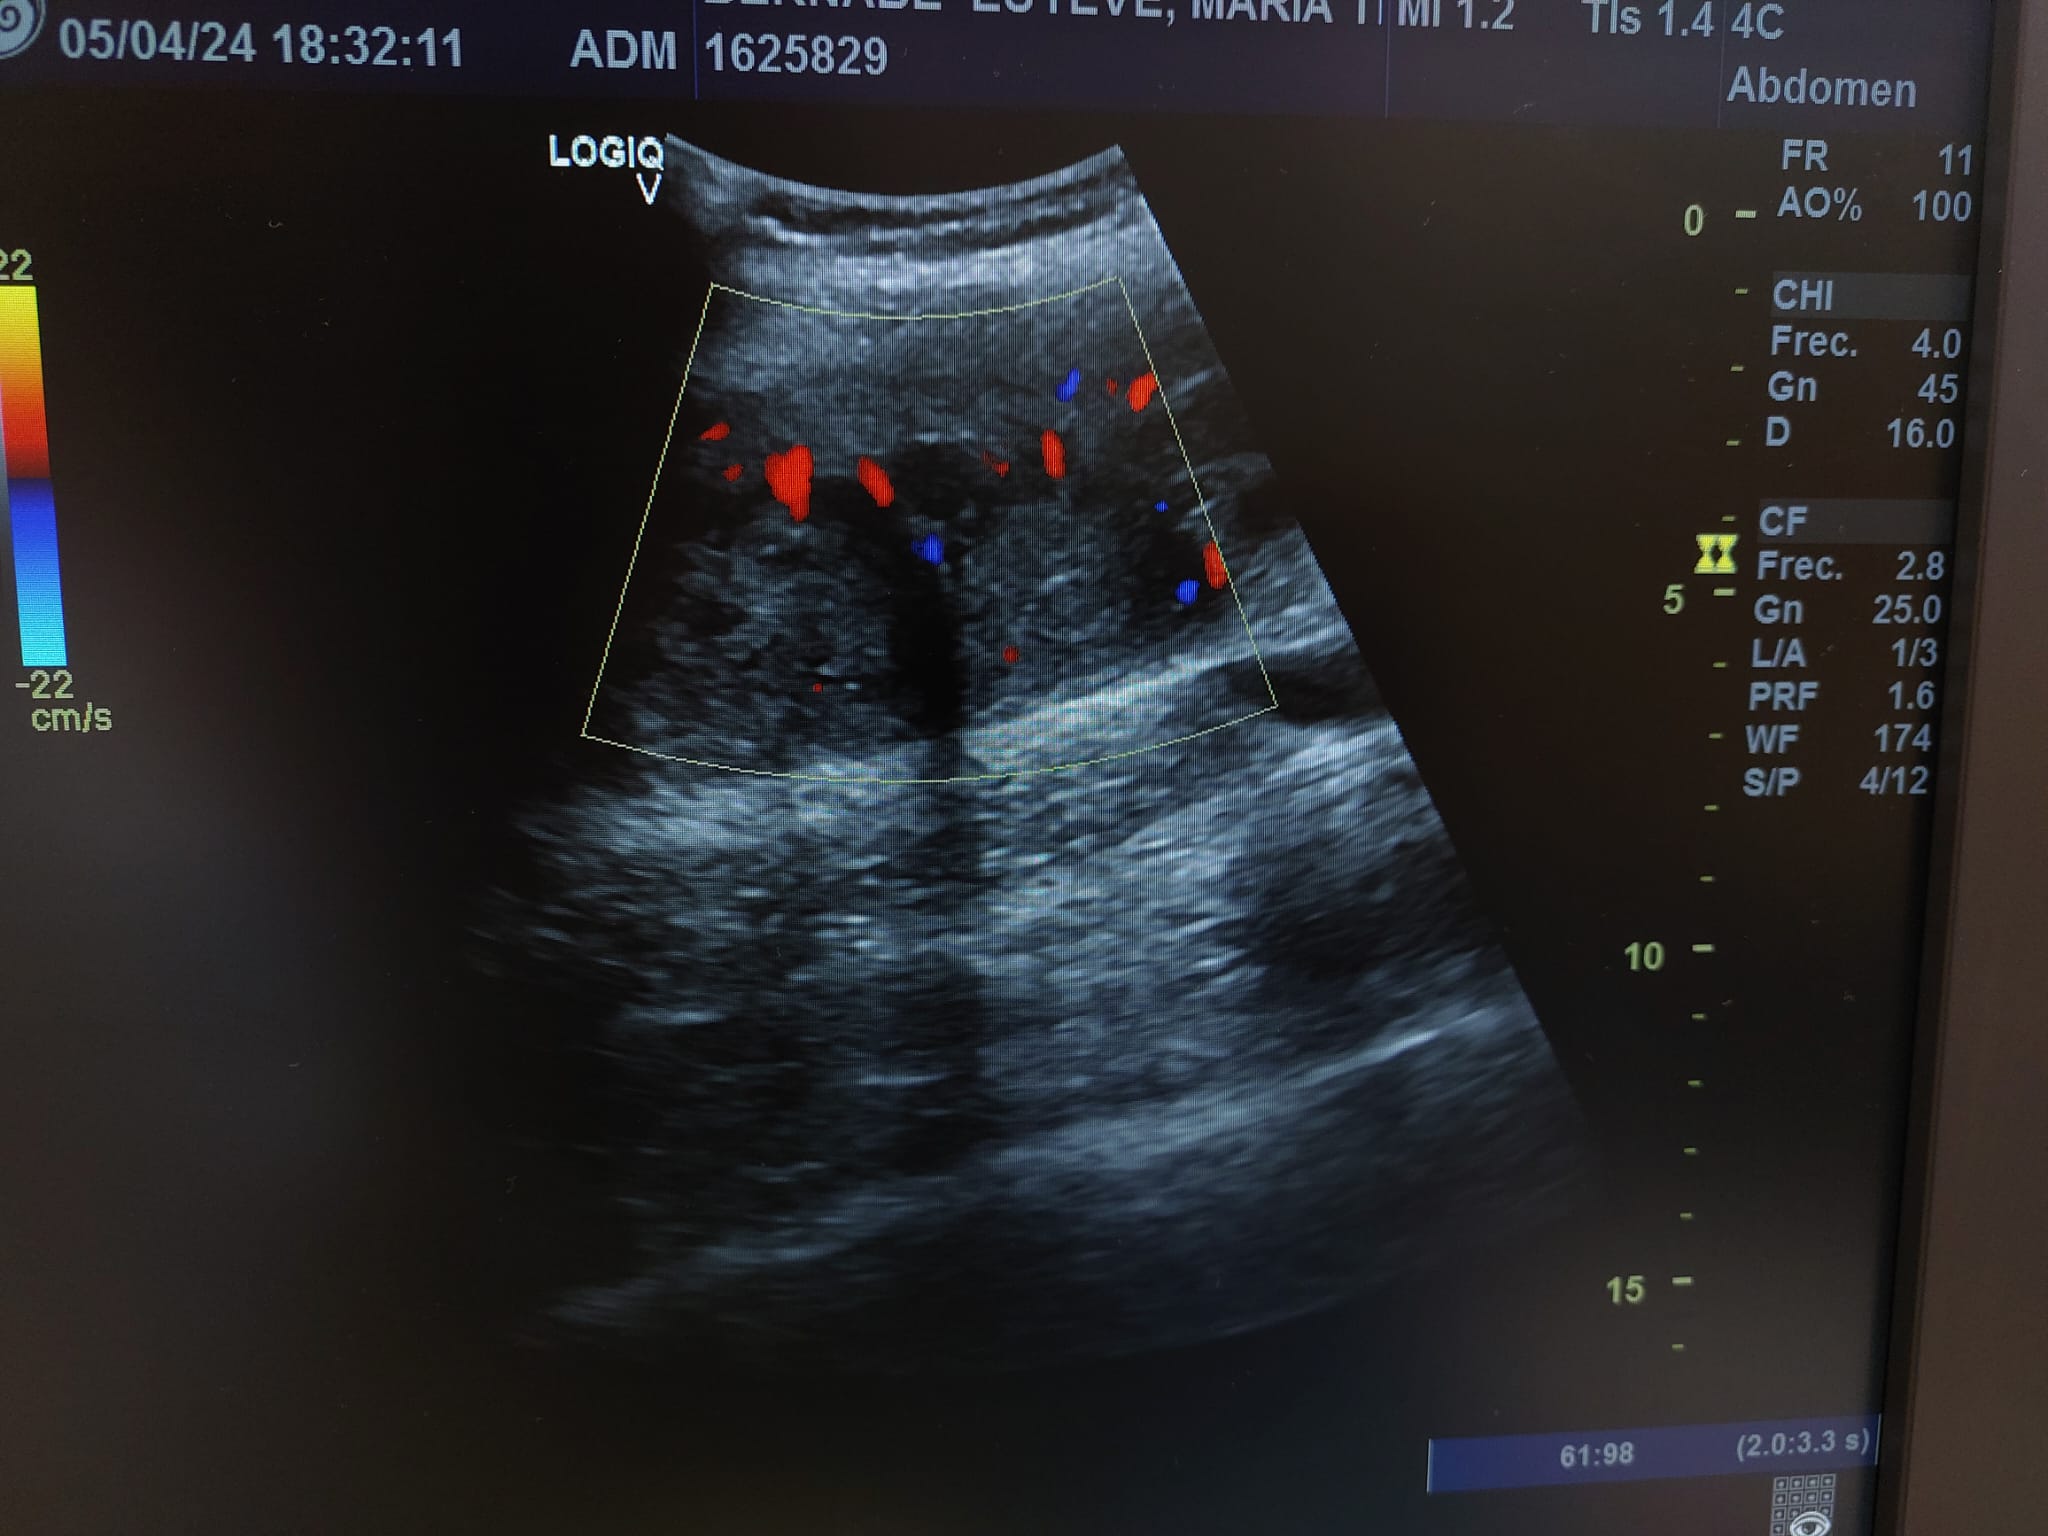

Se realiza ecografía observando colección anecoica a nivel muscular compatible con hematoma organizado, de aproximadamente 7 x 4 cm.

En el seguimiento se observa evolución tórpida sin mejoría clínica y en la ecografía de control se observa aumento notable de tamaño respecto al previo, estructura heterogénea de imagen anecoica con septos internos. Se aprecia edema intramuscular perilesional y captación al activar el Doppler. Se plantea la posibilidad de un hematoma sobreinfectado o, debido a su importante crecimiento, una probable etiología neoplásica. Tras hallazgos descritos en consulta, COT solicita de forma urgente la realización de RNM y biopsia de la lesión. Posteriormente, el resultado de las pruebas complementarias confirman diagnóstico de sarcoma histiocítico.